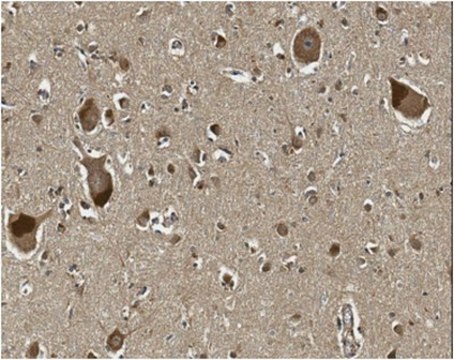

Immunohistochemistry Analysis: A 1:250 dilution from a representative lot detected Oligodendrocyte transcription factor 2 (OLIG2) in human cortical brain section tissue.

This Anti-Oligodendrocyte transcription factor 2 (OLIG2 antibody is validated for use in WB, IH(P) for the detection of Oligodendrocyte transcription factor 2 (OLIG2.